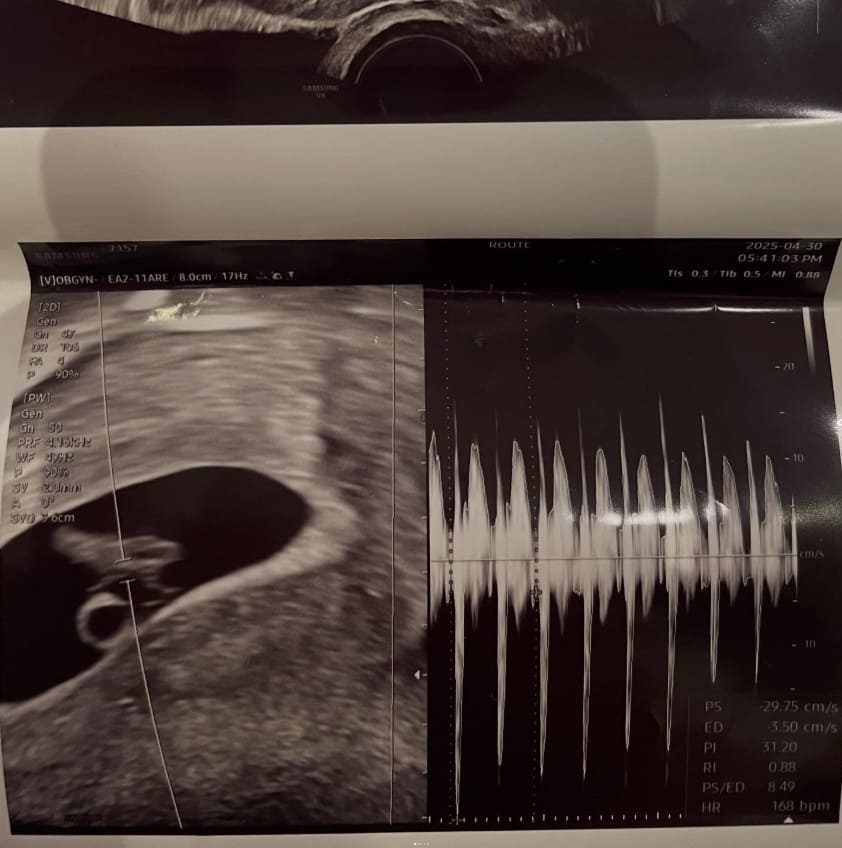

2025년 5월 2일, 서민재(개명 후 서은우)는 본인의 인스타그램 계정에 아래와 같은 사진을 게시했습니다.

해당 게시물에는 태아의 심장 박동이 담긴 초음파 사진과 함께, 남자친구로 보이는 인물과 다정하게 찍은 커플 사진이 포함돼 있었으며, 상대방의 이름·학교·학번·부친 직장 등 상세 신상까지 언급돼 논란이 시작됐습니다.

서민재 인스타그램 (2025.04.30 촬영 기준)

| 2025.05.02 | 초음파 사진 공개 | 서민재가 인스타그램에 “아빠 된 거 축하해” 글과 함께 초음파 사진 업로드 |

A. 본인이 초음파 사진을 SNS에 직접 게시하며 공개한 내용이며, 병원명은 비공개 상태입니다.